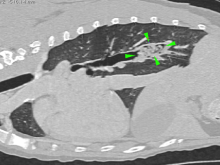

CT Visualisation of Deep Vegetal Foreign Bodies

Soft Tissue Referral Team take advantage of the Diagnostic Imaging Department for the visualisation of deep vegetal foreign bodies ...